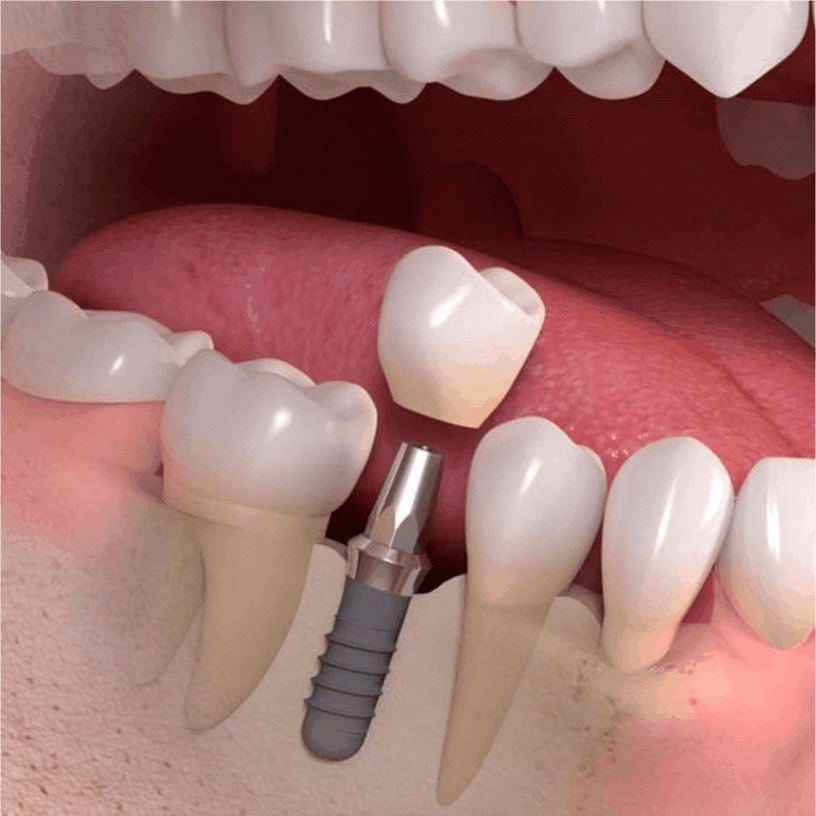

Para se submeter a um implante dentário, o paciente deve ter uma boa saúde bucal, ossos mandibulares saudáveis e estar livre de doenças periodontais ativas. Uma avaliação odontológica é necessária para determinar a viabilidade do implante.

O procedimento é realizado sob anestesia local, o que minimiza qualquer desconforto durante a cirurgia. Algumas pessoas podem sentir um leve desconforto após a cirurgia, mas isso pode ser controlado com analgésicos recomendados pelo dentista.